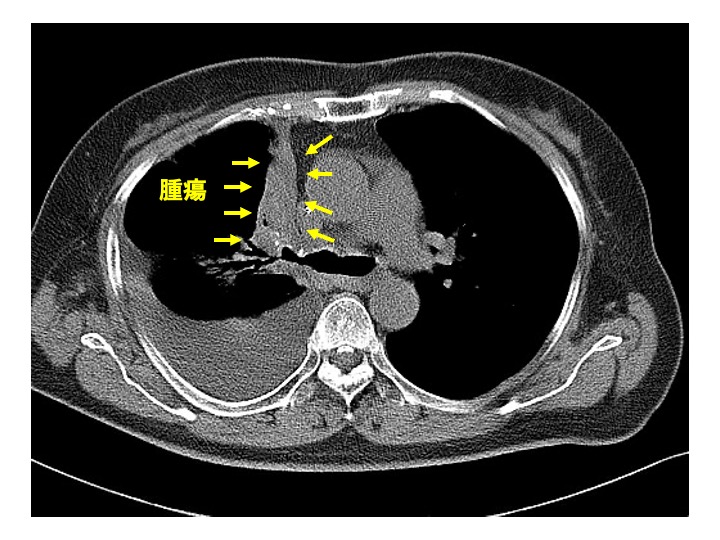

腫瘍領域の抽出には、Vision Transformerを利用した医用画像のセグメンテーションモデルMedSAM2(4)を使用しました。本モデルは Segment Anything Model 2 を医用画像向けに拡張した手法であり、1スライスに数点のプロンプトを入力し領域抽出をすると、他のスライスまで自動抽出が可能です(Fig.2)。実行は、Google Colabratory上のPython環境(GPU: NVIDIA Tesla T4)で行いました。

腫瘍の領域抽出は、専門医による手動設定が一般的ですが、大量の画像に対してスライスごとに領域を設定するため作業負荷の大きさが課題です。本検討では、MedSAM2を使うことで領域抽出の省力化を図りました。具体的には、1画像に約8スライスの腫瘍領域があったことから、1/8の作業時間短縮ができました。さらに、手作業による領域の描画を数点のプロンプト入力に代替することで、1/2以上の時間短縮ができたと考えられ、計1/16以上の時間短縮ができたと考えます。

現在のスライスの画像と領域抽出で取得したマスク画像の特徴を基に、次のスライスを推論する。

領域抽出処理の流れは以下の通りです:

- CT画像をスライス単位で読み込む

- 1スライスの腫瘍領域に点プロンプトを入力

- MedSAM2を適用し、他のスライスにおいて領域抽出およびバイナリマスク生成

- 得られたマスクをradiomics特徴量の抽出に使用

この際、階調は縦隔条件(window level=l40、window width=400)で固定し、MedSAM2による推論をしました。また、マスク画像と元画像で座標系を一致させました。